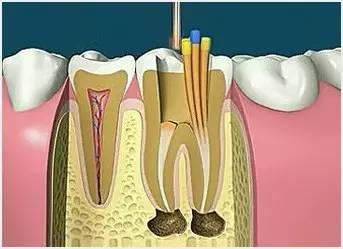

6、根管充填

封閉整個根管系統(tǒng)、堵塞主根管和側(cè)副根管出口、防止微生物和液體的滲漏。無論是側(cè)方加壓法還是垂直加壓法,應(yīng)做到根管充填致密,根管充填后X線片上無根管腔隙,也不能超出根尖孔。

7、根管打樁

因牙體缺損過多,導(dǎo)致牙的強度(承受力量的性能)大幅度下降,不能很好地承受咀嚼力量。打樁的目的是增加牙根及牙冠的強度,增加患牙的穩(wěn)固。